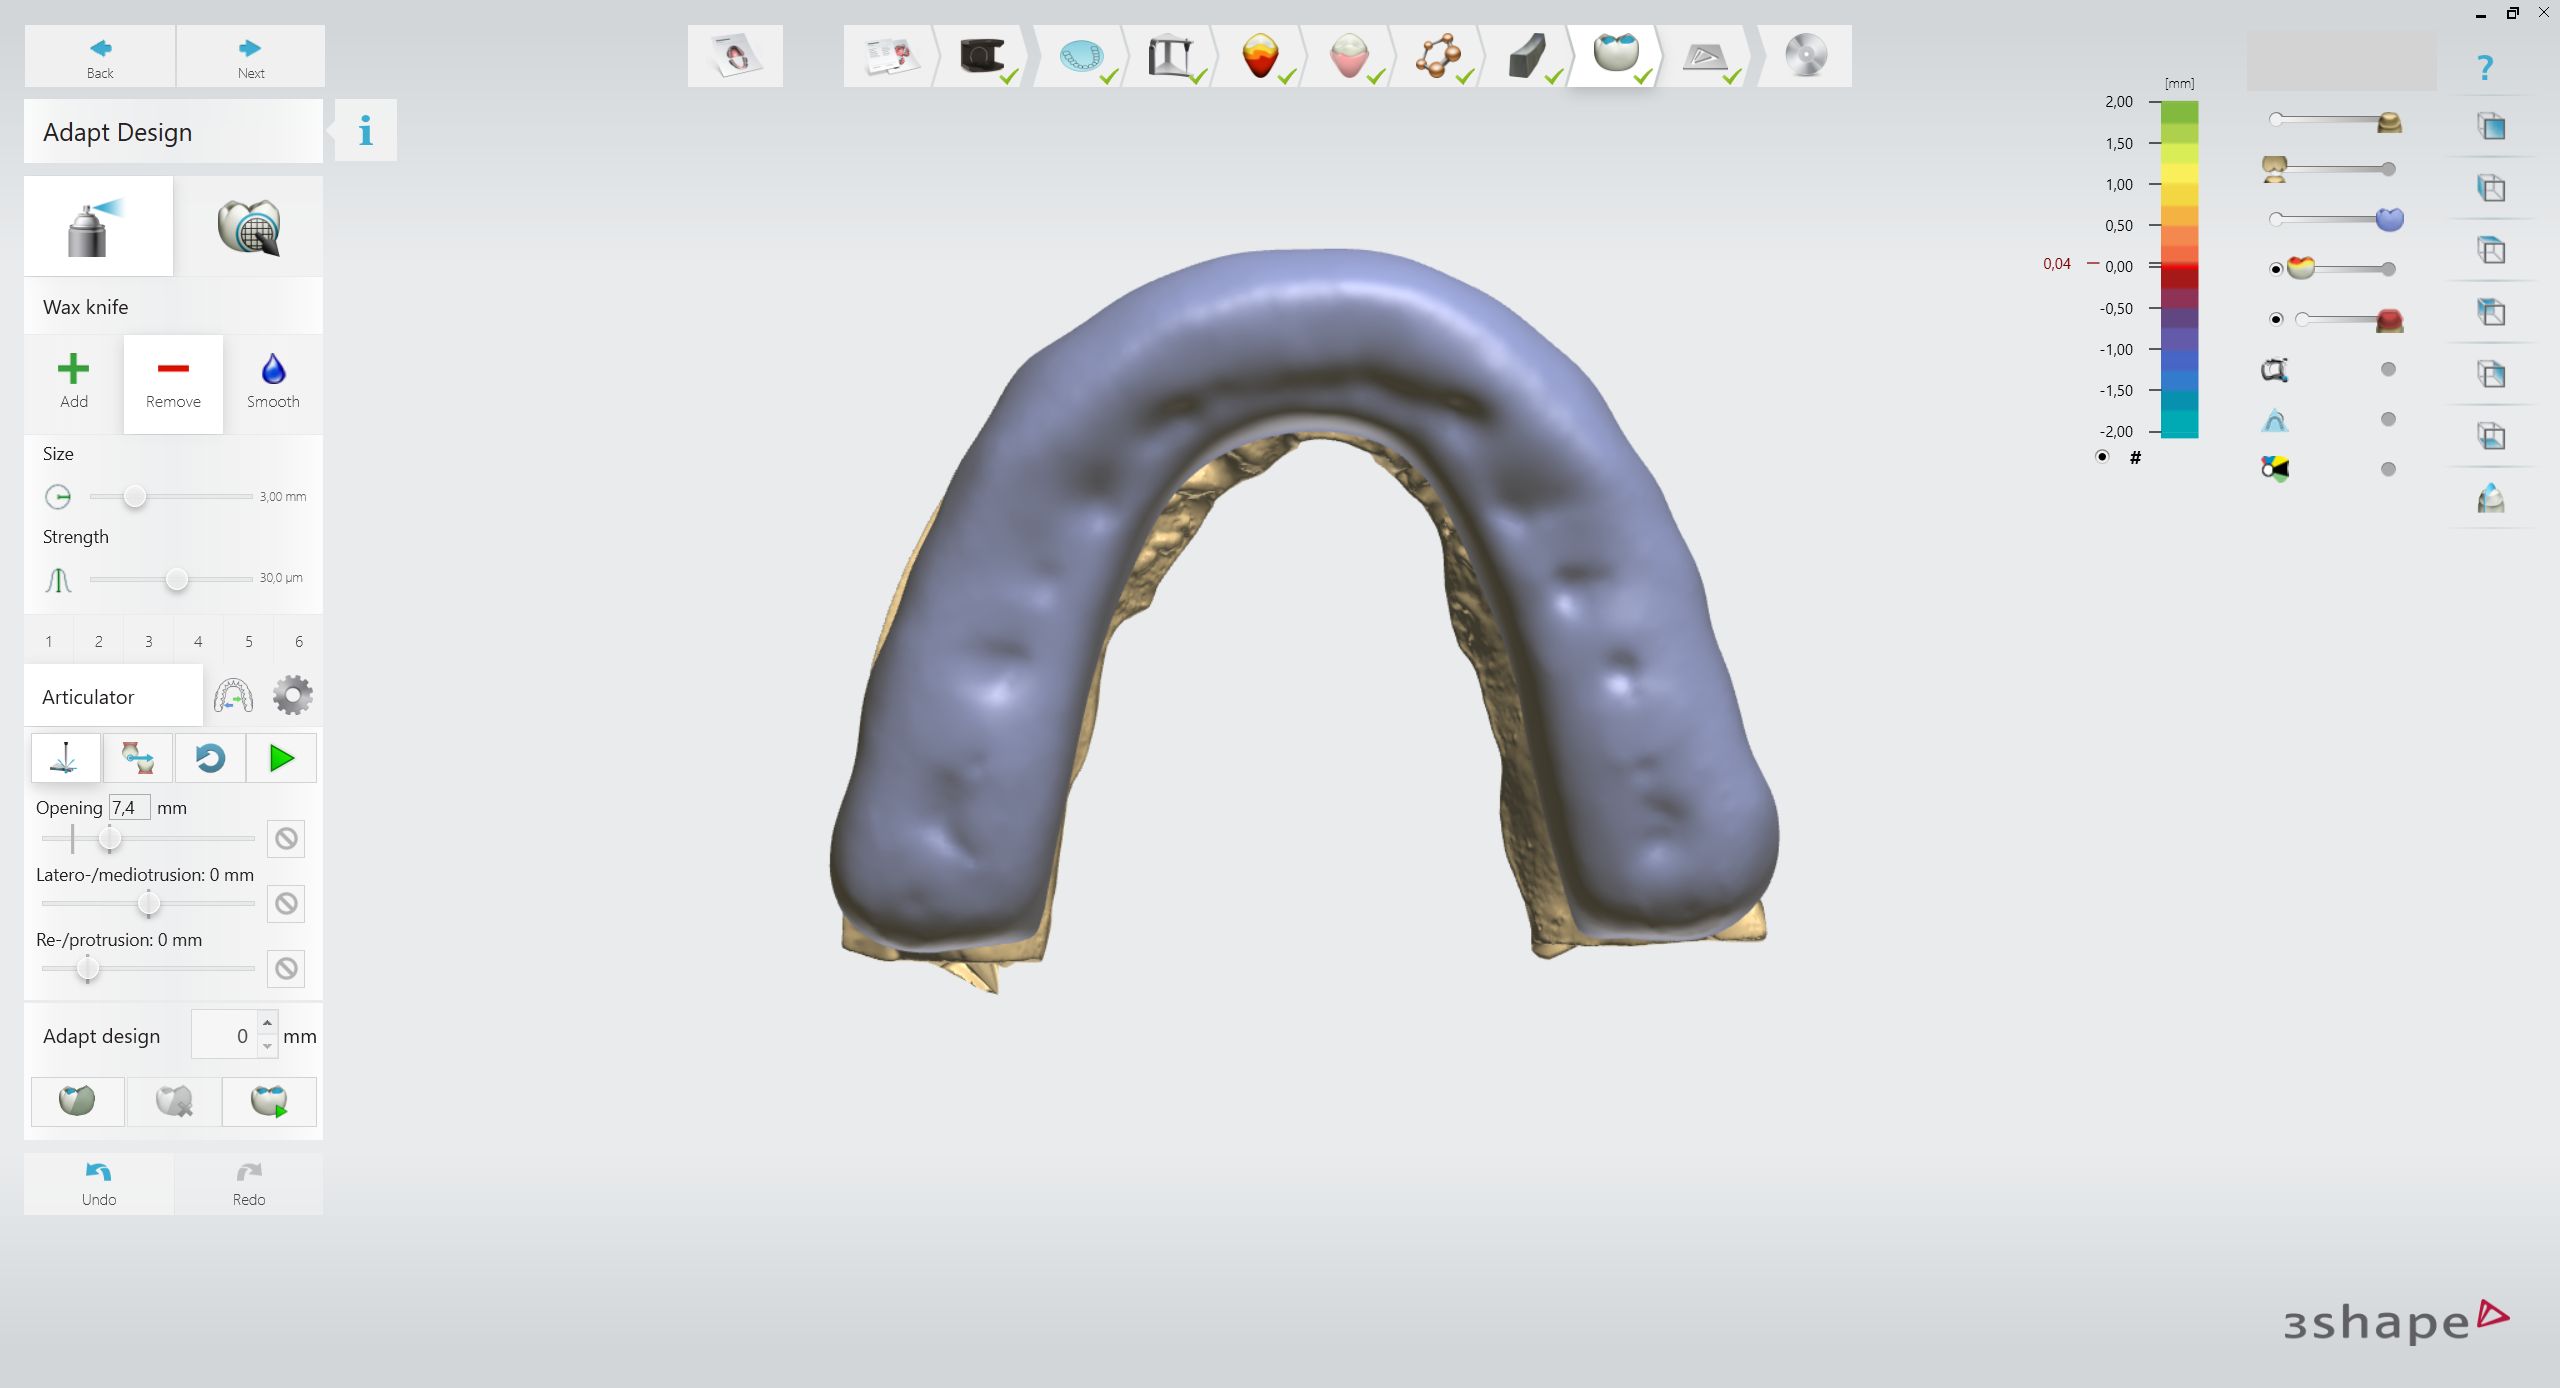

3shape Smile Design

Immerse yourself in the artistic beauty of 3shape Smile Design through substantial collections of inspiring images. blending traditional techniques with contemporary artistic interpretation. transforming ordinary subjects into extraordinary visual experiences. The 3shape Smile Design collection maintains consistent quality standards across all images. Ideal for artistic projects, creative designs, digital art, and innovative visual expressions All 3shape Smile Design images are available in high resolution with professional-grade quality, optimized for both digital and print applications, and include comprehensive metadata for easy organization and usage. Our 3shape Smile Design collection inspires creativity through unique compositions and artistic perspectives. Instant download capabilities enable immediate access to chosen 3shape Smile Design images. Our 3shape Smile Design database continuously expands with fresh, relevant content from skilled photographers. The 3shape Smile Design collection represents years of careful curation and professional standards. Diverse style options within the 3shape Smile Design collection suit various aesthetic preferences. Multiple resolution options ensure optimal performance across different platforms and applications. Professional licensing options accommodate both commercial and educational usage requirements. Each image in our 3shape Smile Design gallery undergoes rigorous quality assessment before inclusion. Time-saving browsing features help users locate ideal 3shape Smile Design images quickly. Advanced search capabilities make finding the perfect 3shape Smile Design image effortless and efficient.